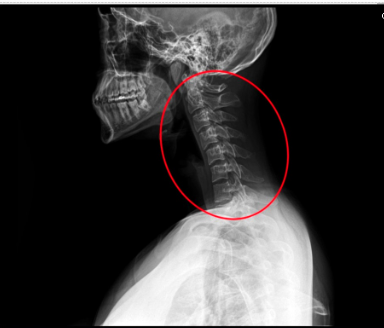

거북목이나 등이 굽었을 때

턱은 왜 아플까요?

이유부터 바로 말씀드릴게요.

우리의 머리는 생각보다 무겁습니다.

성인 기준으로 약 4~5kg 정도 되는데,

거북목 굽은등 자세가 되면

이 무게가 그대로 앞쪽으로 쏠리게 됩니다.